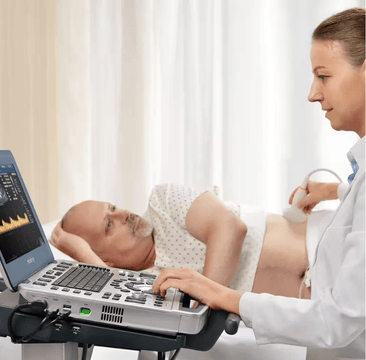

While the healthcare industry has been making a steady, decades-long shift from volume to value,?Mindray.has been steadfast in our mission to advance medical technologies to make high-quality healthcare more accessible. With reimbursement rates declining and hospitals feeling pressure to cut costs while managing increasing patient volumes, clinicians continue to look to?ultrasound?for a cost effective, real-time alternative to more invasive diagnostic solutions. But with the increase of itŌĆÖs prevalence and cliniciansŌĆÖ reliance, how can shrinking budgets support the continuous evolution of ultrasound technology? Enter Mindray.

At Mindray, we equip our partners and their clinicians with ultrasound solutions they wonŌĆÖt soon outgrow.?Living TechnologyTM?is MindrayŌĆÖs approach to easily upgradable ultrasound enhancements based on our advanced, proprietary technologies. These upgrades secure product investment protection by ensuring that?Mindray ultrasound systems?remain at the?leading-edge of imaging performance?excellence throughout the life cycle. As clinicians continue to provide outstanding care, they shouldnŌĆÖt have to worry about whether or not the ultrasound system theyŌĆÖre working with is up-to-date and reliable. And hospital finance departments shouldnŌĆÖt have to worry about being able to afford to keep every?ultrasound machine system-wide up-to date. Technology should make the job easier, give peace of mind, and empower you and your teams to work and care for your patients with confidence.